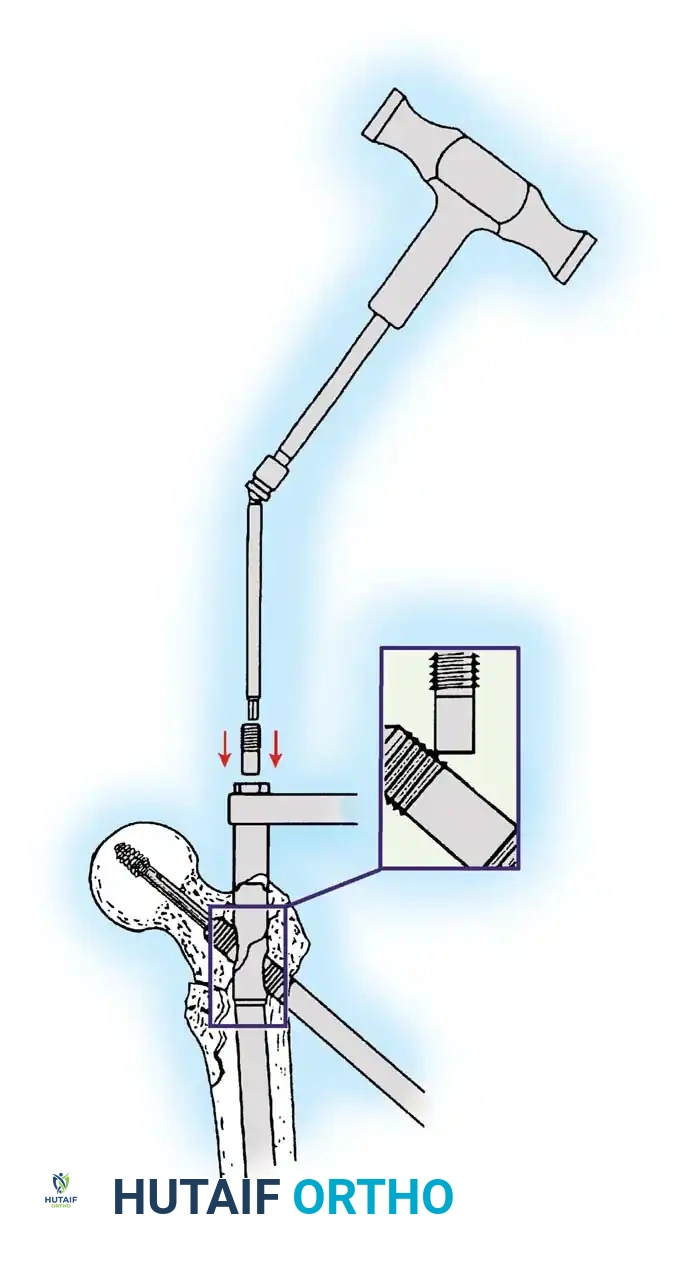

5. Intramedullary Nailing (For Unstable Fractures)

If a cephalomedullary nail is chosen, the entry point is established at the tip of the greater trochanter (or slightly medial, depending on the specific implant design).

Insertion of the cephalomedullary nail down the femoral shaft. Care must be taken not to distract the fracture site during insertion.

After the nail is seated, the proximal lag screw(s) are inserted through the nail into the femoral head, adhering to the same TAD principles.

Proximal locking of the cephalomedullary nail. The targeting guide ensures accurate trajectory into the femoral neck.

Finally, distal locking screws are placed to control rotation and maintain length.